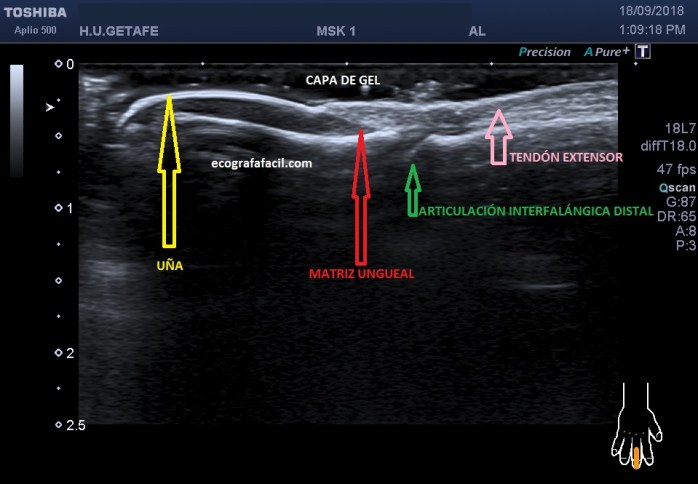

En estructuras muy superficiales, como estructuras que se encuentran inmediatamente bajo la piel lo que haremos será poner mucho gel y posar levemente nuestra sonda sobre el gel (foto 2) y no sobre la piel para no deformarla en absoluto y poder estudiar, por ejemplo lesiones cutáneas (Dermatología) o subcutáneas.

In very superficial structures, such as structures that are immediately under the skin, what we will do is put a lot of gel and slightly place our probe on the gel and not on the skin so as not to deform it at all and be able to study, for example skin lesions (Dermatology) or subcutaneous.